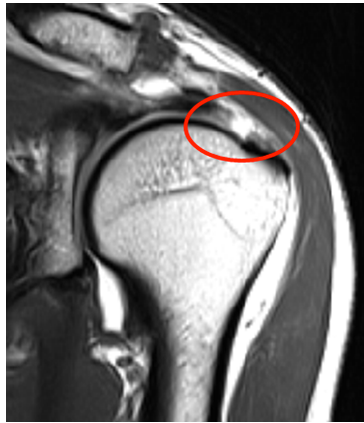

MRI: 회전근개의 손상 정도를 정확하게 파악할 수 있으며, 힘줄의 파열 및 근육의 상태를 세밀하게 확인할 수 있습니다.